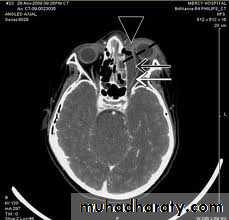

Complications of Acute Sinusitis

In most cases sinusitis is uncomplicated and spread of infection beyond the walls of the sinus is uncommon. Complications may follow an acute infection, but are most frequent during an acute exacerbation of chronic sinusitis. They can be divided into:• Orbital complications (orbital cellulitis and orbital abscess).

• Osteomyelitis (maxilla or frontal bone).

• Intracranial complications (meningitis, intracranial abscess,

cavernous sinus thrombosis).

Orbital Complication

Occurs more commonly in childIll with spiking pyrexia

Chemosis and diplopia.

Proptosis and painful eye movement.

Color blindness.

Treatment:Emergency condition?

Immediate admission.

Start with IV antibiotics + Decongestant

If there is abscess formation Drinage.